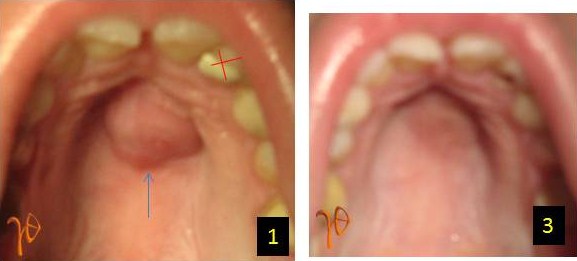

Παρουσιάζεται μία τέτοια περίπτωση οδοντογενούς αποστήματος, το οποίο εκδηλώθηκε σε νεαρή 16 χρονών και οφειλόταν στον αριστερό άνω πλάγιο τομέα (Εικ. 1). Η βλάβη επεκτεινόταν στη μεσότητα της υπερώας, είχε διαστάσεις 2 X1,5 cm και ιστορικό εμφάνισης περίπου μίας εβδομάδας με αντιβιοτική κάλυψη χωρίς αποτέλεσμα. Η πανοραμική ακτινογραφία (Εικ. 2) δεν βοήθησε διαγνωστικά σε αντίθεση με την κλινική εξέταση η οποία ήταν ενδεικτική για επικρουστική ευαισθησία του #22.

Εικ. 1: Υπερώια διόγκωση(βέλος), #22(σταυρός), Εικ. 2: Συμμετρικές διαυγάσεις χωρίς διαγνωστικό ενδιαφέρον (βέλη), #22 (σταυρός), Εικ. 3: Δέκα μέρες μετά την επέμβαση στο #22

Με την διάνοιξη του υπεύθυνου δοντιού έγινε δυνατή μια αρχική παροχέτευση της αποστηματικής συλλογής της υπερώας. Προγραμματίστηκε ενδοδοντική θεραπεία και ακρορριζεκτομή του #22. Δέκα μέρες μετά την επέμβαση, η σταδιακή αποκατάσταση του φυσιολογικού στην περιοχή της αρχικής υπερώιας διόγκωσης(Εικ. 3).